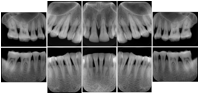

In most standard cases, images are oriented in structured layouts. These structured displays are useful to be shared between providers for reference purposes.

Table OO.1.1-1 shows structured display standard templates, where Viewset ID is based on the Japanese Society for Oral and Maxillofacial Radiology (JSOMR) classification provided by JIRA (Japan Medical Imaging and Radiological Systems Industries Association, www.jira-net.or.jp). Expected or typical teeth to be imaged location, region and designation codes are based on ISO 3950-2010, Dentistry - Designation system for teeth and areas of the oral cavity. For all the hanging protocols listed in OO.1.1-1, the value to use for Hanging Protocol Creator (0072,0008) is "JSOMR" and the value to use for Hanging Protocol Name (0072,0002) does not include "JSOMR" (e.g., "DL-S001A", not "JSOMR DL-S001A").

Table OO.1.1-1. Hanging Protocol Names for Dental Image Layout based on JSOMR classification